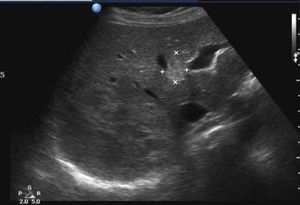

Liver- most likely a hemangioma but focal fatty sparing is a differential.

Maybe hepatic hemangioma?

Liver with some solid mass lesion , multiple hypoechoic lesion seen in lower part too.. can it be liver abscess?

Liver/Hemangioma. Thank you guys☺️👍🏻